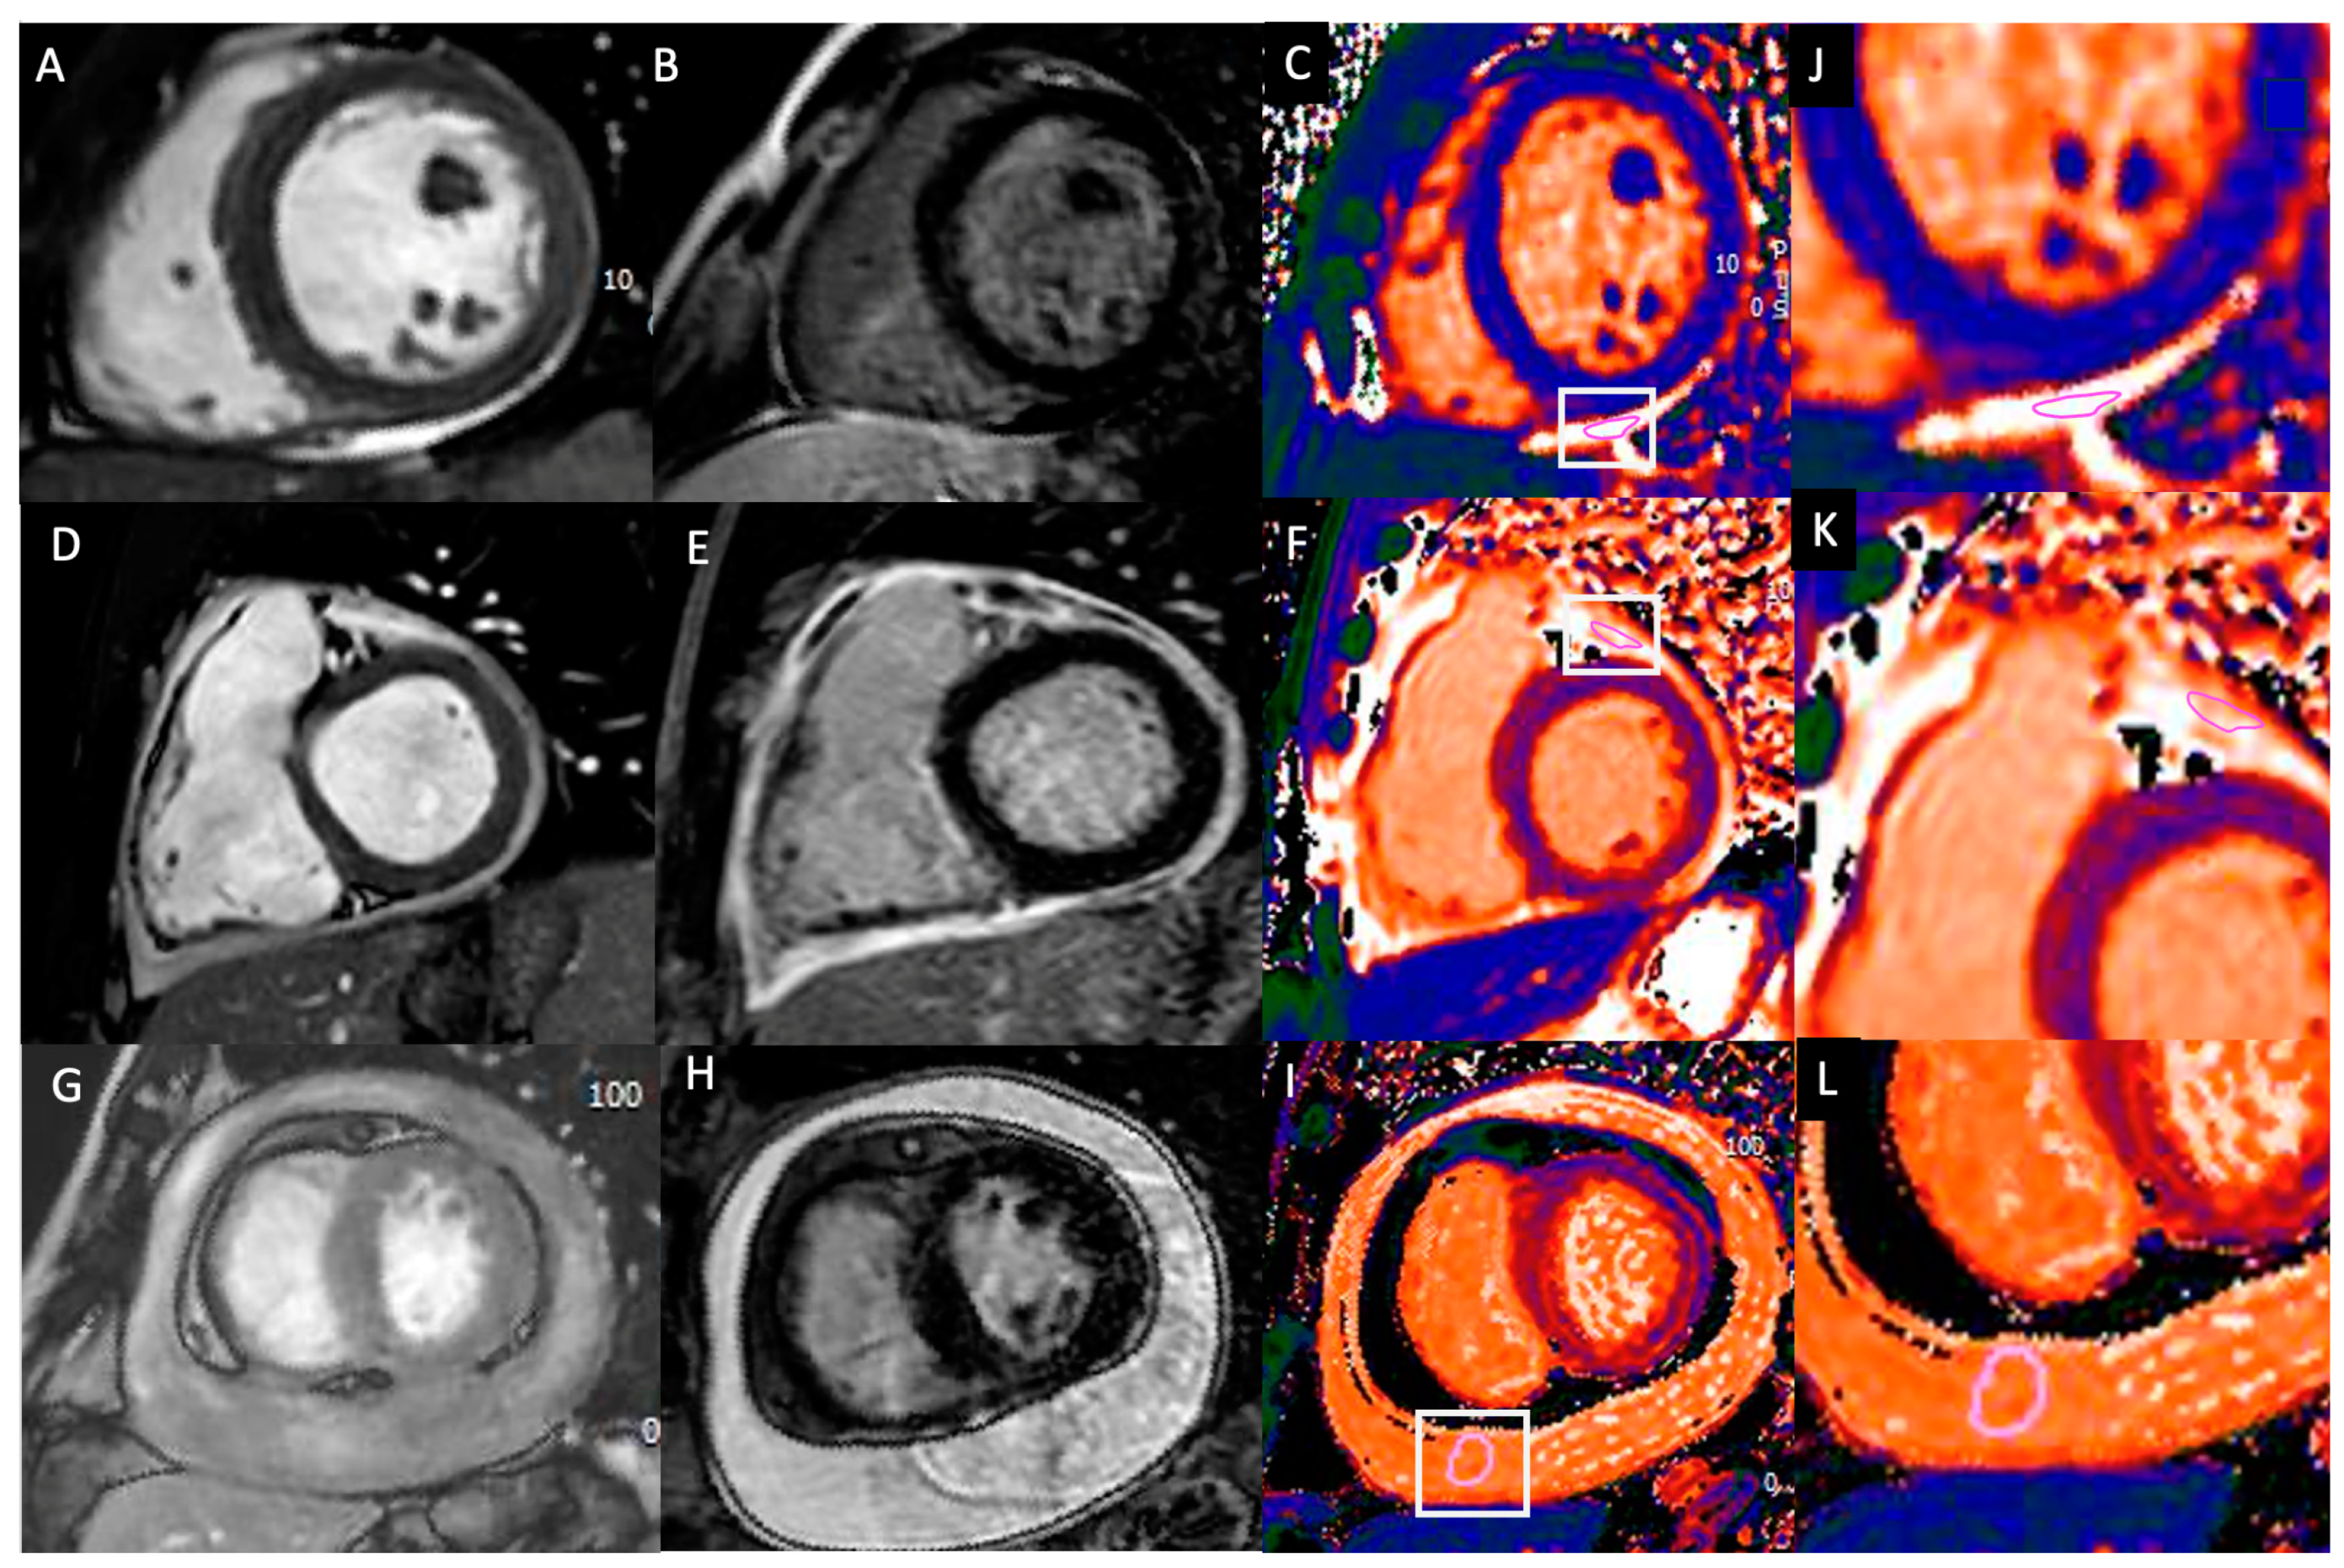

3.2. CMR Features in Acute Pericarditis Patients

| LGE pericardial enhancement, n (%) | 23 (66%) | / | / |

| Pericardial T2 STIR, n (%) | 28 (80%) | / | / |

| Pericardial T1 mapping, ms | 2137 ± 519 | 3268 ± 362 | 0.001 |